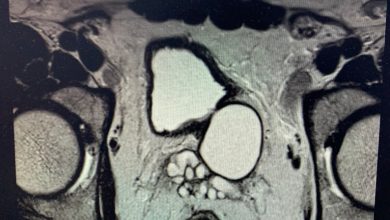

نجح فريق طبي في مستشفى النور بمكة المكرمة بإجراء عملية جراحية لواحدة من أندر الحالات الطبية وأكثرها غرابة وهي “متلازمة…

أكمل القراءة » -